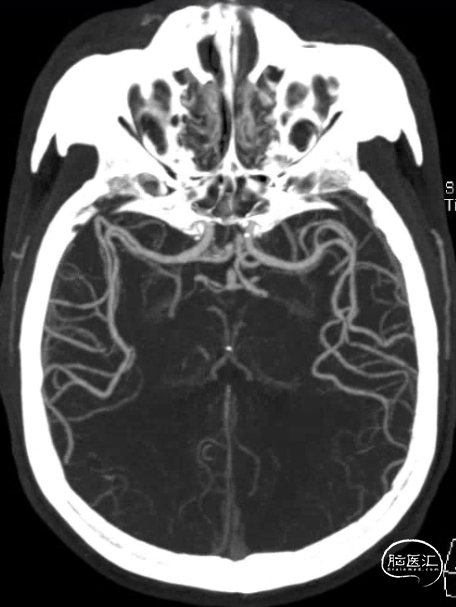

术前影像学检查

急诊头颅MRI+MRA示:双侧额叶少许小缺血灶;脑动脉硬化,伴左侧大脑前动脉纤细及多组脑动脉局限性狭窄。

CTP示:右侧额颞顶枕叶、左侧额叶Tmax稍延长,提示侧枝代偿尚可。

DSA:

3D测量。

90cm 长鞘+5F 125cm Tethys®中间导引导管,Synchro支撑力不足,更换3m 0.014inch微导丝。

引入加奇1.75×9mm SacSpeed®球囊扩张导管。

预扩张后造影。